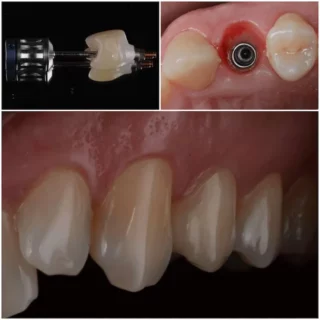

3. Az implantáció – a mesterséges gyökér beültetése

A beavatkozás helyi érzéstelenítésben történik, így a páciens semmit nem érez.

Az implantológus az előre meghatározott pozícióba beülteti a titánból készült műgyökeret az állcsontba.

Ez a kis csavar tölti be a foggyökér szerepét – stabil alapot ad a későbbi koronának vagy hídnak.

Az implantáció általában 30–60 percet vesz igénybe, teljesen fájdalommentesen.

5. A felépítmény és a végleges fogpótlás elkészítése

A gyógyulási idő leteltével az implantátumra egy apró felépítmény (csonkfej) kerül, erre rögzítjük a végleges koronát vagy hidat.

A SmileCenter fogtechnikusai digitális lenyomat alapján készítik el a pótlást, CAD/CAM technológiával – így az illeszkedés, a szín és a forma milliméter pontos.

A végeredmény természetes hatású, kényelmes és tartós.

Sok páciens el sem tudja különíteni az implantátumot a saját fogaitól – pontosan ez a cél.